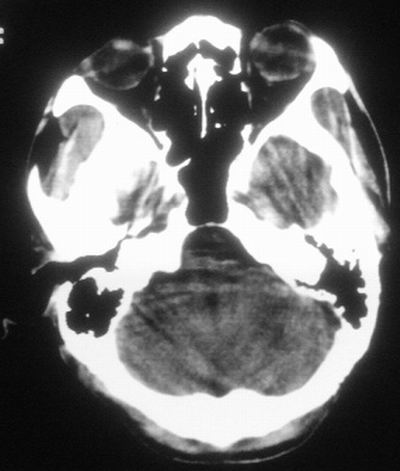

患者,男,30岁,右侧面部麻木,右上肢活动受限27小时。pe:神清、呼吸平稳,口角左歪,右上肢活动受限,右手掌握力消失,右侧躯体痛觉减退。

第一次颅脑ct扫描:左侧额顶叶血肿。

治疗三天后复查ct:除左侧额顶叶血肿外。左侧额叶另见片状低密度灶,密度不均匀,境界不清;考虑脑梗塞。